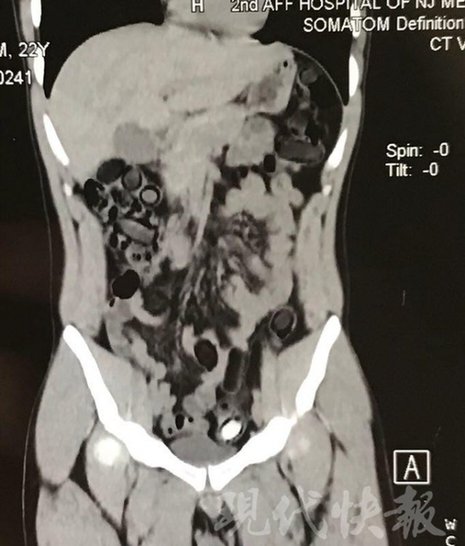

由于毒品在體內(nèi)一旦泄露有可能致命,警方第一時間將阿永帶到醫(yī)院進行檢查。CT 掃描的結(jié)果顯示,阿永體內(nèi)布滿了密密麻麻的白色圓柱狀固體,就像一粒粒的蠶蛹。在南京市公安局鼓樓分局二板橋派出所,阿永分四次排出了毒品,毛重369.99克。經(jīng)訊問,阿永交代了自己全部的犯罪事實。目前,阿永已被刑事拘留。